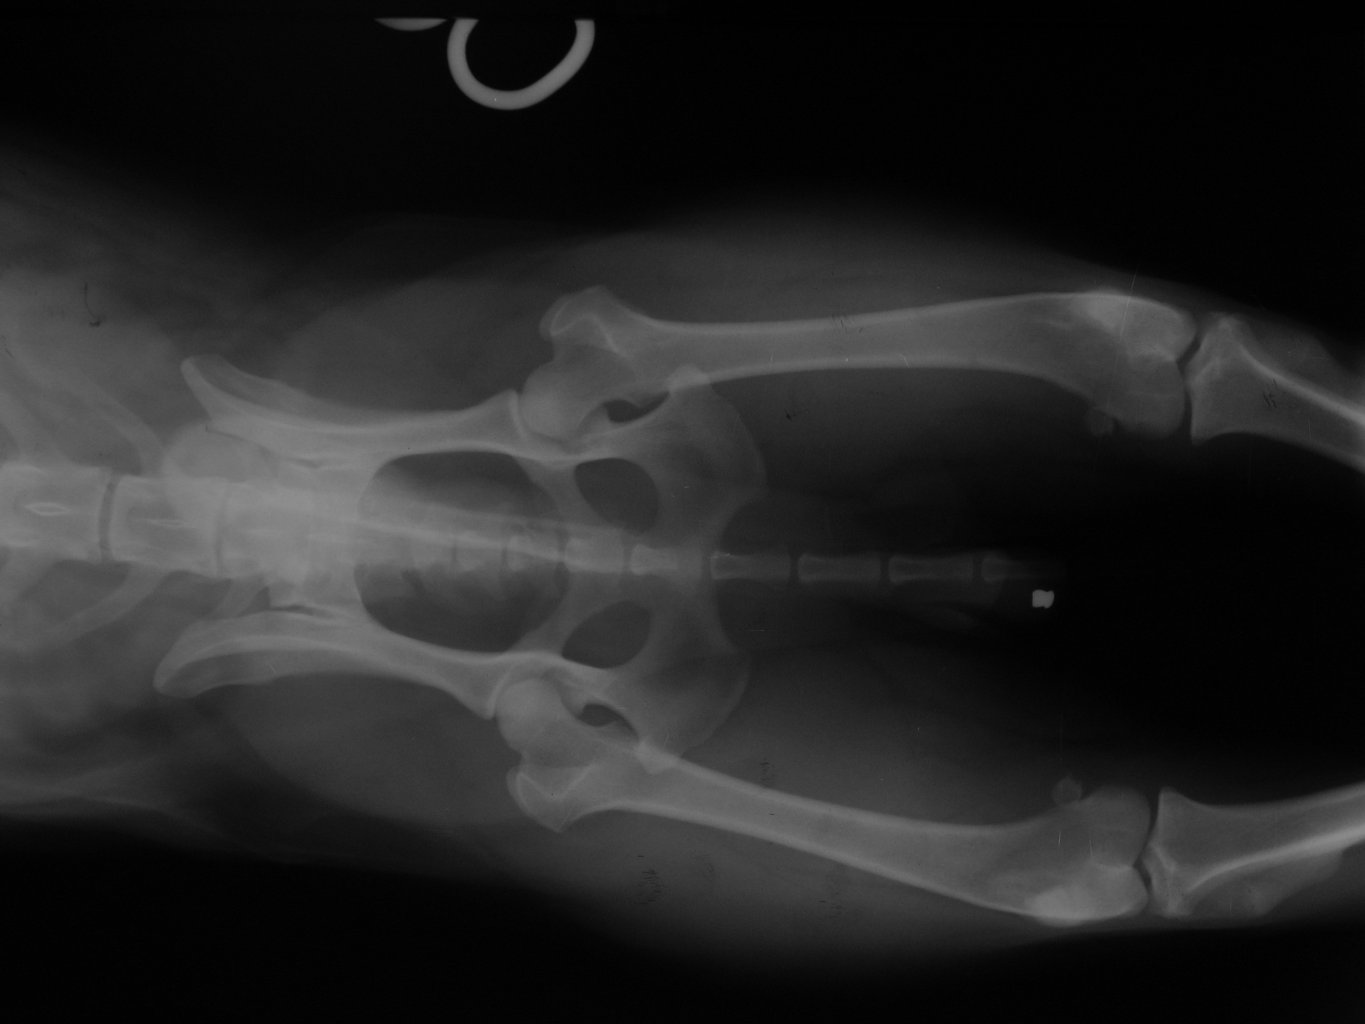

Fotogalerie